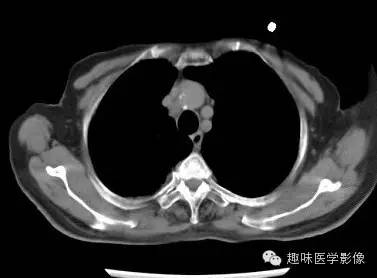

双肺多发无壁低密度区,以右肺下叶底部为主。右肺下叶见大片不规则实变阴影伴多发空洞影,实变肺组织内见支气管气象,右肺下叶支气管局部显示不清。纵隔内见淋巴结。右侧胸腔内见积液影,邻近胸膜肥厚。主动脉、冠状动脉钙化。

右肺下叶肺脓肿、肺炎伴胸腔积液,肺气肿、肺大泡。

右胸廓变小,心影右移;右肺下叶多房性空洞,空洞内未见明显液平面,右下肺病变应该是下叶阻塞性肺炎,实变肺组织内见支气管气像,邻近胸膜增厚,并合并胸腔积液,支持肺脓肿。